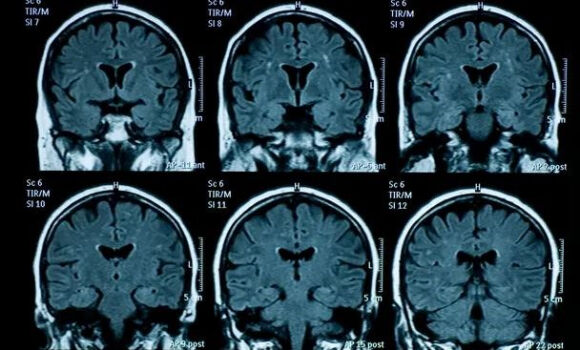

Sức khỏe tâm thần giảm sút đi đôi với những thay đổi về cấu tạo vật lý của não bộ ở thiếu niên. (Nguồn: Getty Images).

Các nhà nghiên cứu đã so sánh hình ảnh chụp cộng hưởng từ (MRI) của 81 thanh thiếu niên sống tại Mỹ được chụp trước thời kỳ đại dịch bùng phát (từ tháng 11/2016-11//2019) với kết quả MRI của 82 thanh thiếu niên chụp trong giai đoạn từ tháng 10/2020-3/2022, khi đại dịch vẫn hoành hành nhưng sau khi các biện pháp phong tỏa đã được dỡ bỏ.

Sự thay đổi về cấu trúc vật lý của não bộ trong quá trình dậy thì - như vỏ não mỏng đi, sự phát triển của đồi hải mã và chất xám - xảy ra ở nhóm được chụp MRI sau phong tỏa nhiều hơn so với nhóm được chụp MRI trước đại dịch.